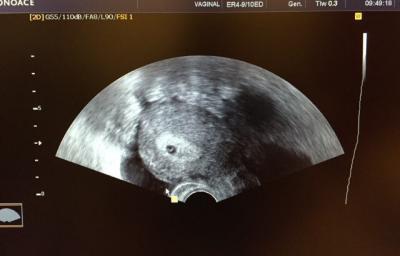

So komme gerade von der KiWu Klinik. Der US sah sehr gut aus. Ab Montag geht es dann wieder zum niedergelassenen Gyn. Bis zur 12.Woche kann viel passieren. Aber ich muss sagen nach den Abbort letztes Jahr bis ich nun beruhigter.